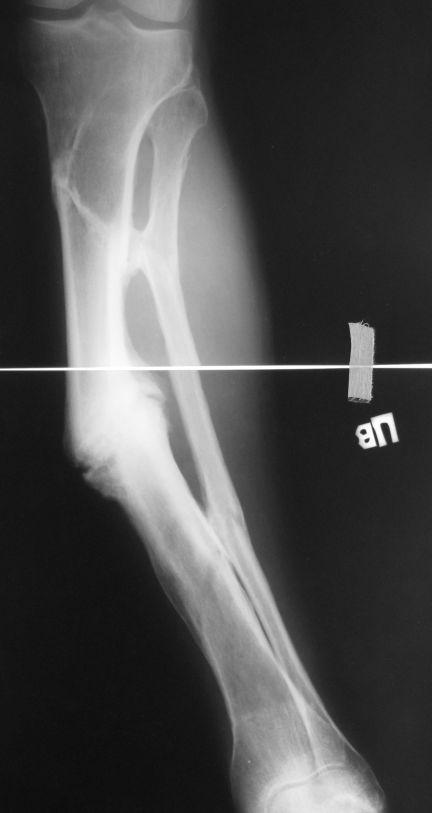

[Ortho] псевдоартроз большеберцовой кости

Уважаемые коллеги. Имеется вот такой псевдоартроз. Планируем БИОС tibia стержнем Chm,

остеотомию малоберцовой и большеберцовой через зону псевдоартроза. Вопрос! Коррекцию

лучше сделать одномоментно во время операции или дозированно в аппарате недели за 2-3, а

потом nailing? И ещё делать нормо или с учетом вальгуса гиперкоррекцию? Заранее спасибо за

советы!